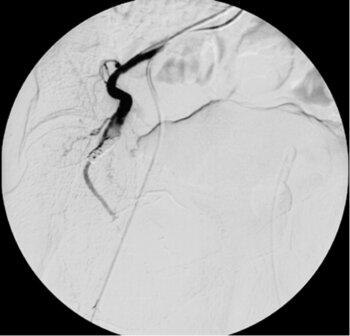

Digitale Subtraktionsangiografie: In der Leber zeigen sich multiple pathologische Anreicherungen, die Tochtergeschwülsten eines Karzinoids entsprechen.

Digitale Subtraktionsangiografie: Einen Monat nach der erfolgten Chemoembolisation, bei der direkt in die Leberarterie ein Medikament zur Tumorbehandlung gegeben wurde (TACE), stellen sich die zuvor zahlreichen Metastasen nicht mehr dar.